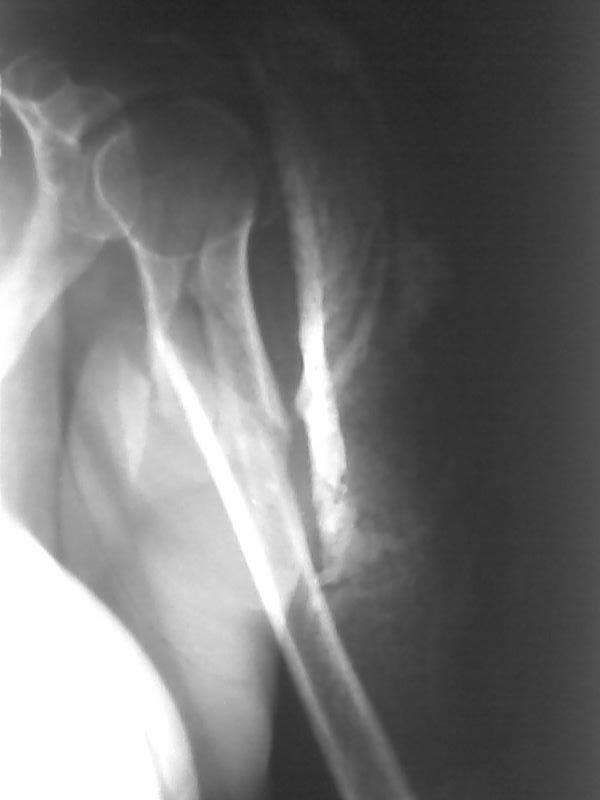

послал Евгений 09 Апрель 2009, 22:53

Высылаю рентгенограммы больной до операции и в гипсовой лонгете. Сейчас больную вообщем-то особо ничего не беспокоит, незначительная болезненность в области перелома при движениях плечом, первые два дня была отечность кисти, которая сейчас исчезла, объем движений в локтевом суставе постепенно увеличивается, отведение плеча пока небольшое. Дистальное блокирование выполнено одним винтом в передне-заднем направлении (через бицепс. Да, клинок мы конечно же заблокировали концевым колпачком. Нас тоже беспокоит возможность развития импиджмент синдрома, надеемся на то, что больная разработает движения в плечевом суставе.